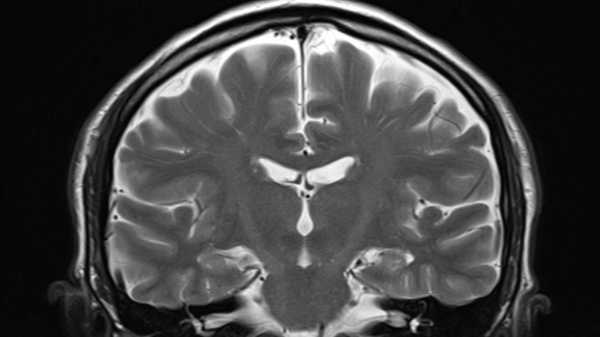

Нове дослідження показує, що повторні удари головою будь-якої інтенсивності можуть з часом підвищити ризик ХТЕ. (Зображення: Klaus Vedfelt/Getty Images)

Досі дослідники вважали, що хронічна травматична енцефалопатія (ХТЕ) — дегенеративне захворювання мозку, пов'язане з повторними травмами голови, яке характеризується проблемами з настроєм, поведінкою, мисленням та пам'яттю, — починається головним чином з накопичення аномального білка в мозку. Цей білок, який називається тау-білком, зазвичай допомагає підтримувати здоров'я нейронів, але в своїй аномальній формі він може їх вбити. Фактично, ХТЕ можна точно діагностувати лише після смерті, оскільки на той час лікарі можуть безпосередньо досліджувати рівень тау-білка в тканині мозку.

У новому дослідженні вчені вивчили тканину мозку 28 людей, яким на момент смерті було від 20 до 51 року. Деякі не мали в анамнезі ударів головою; деякі займалися контактними видами спорту, але не мали ознак ХТЕ; а в інших була рання стадія ХТЕ, згідно з аналізом їхньої тканини мозку.

У лобовій корі головного мозку — ділянці, яка приймає на себе основний тягар ударів головою — дослідники виявили 56% падіння кількості специфічних нейронів, які допомагають різним ділянкам мозку спілкуватися. Ця втрата проявлялася незалежно від того, чи було у спортсменів помітне накопичення тау-білка, що є ознакою хронічної травми голови.